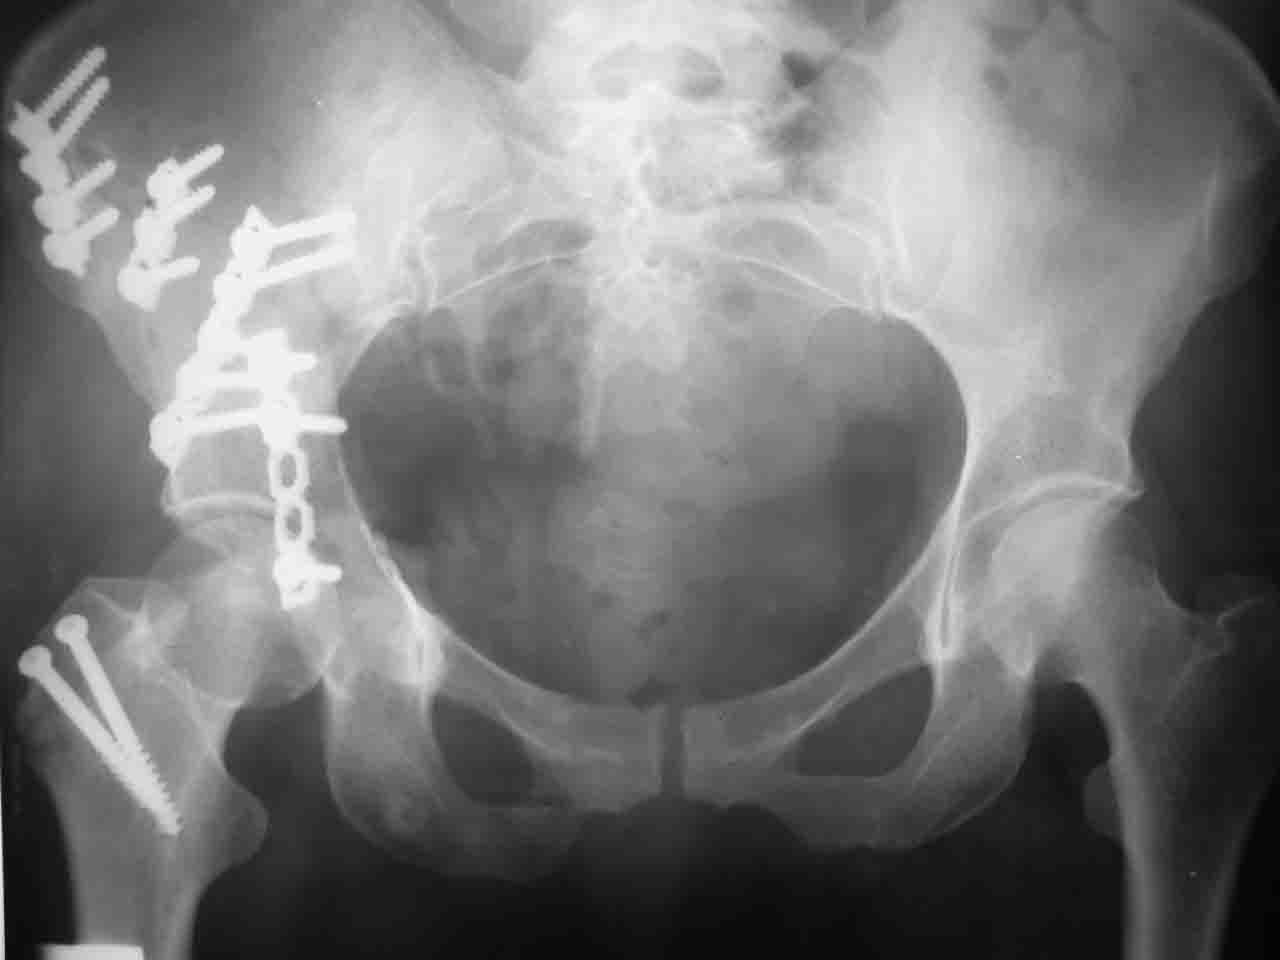

Уважаемые коллеги,43 летний мужчина, попав в автоаварию 13.10.2004, получил оскольчатый перелом обеих колонн левой вертлужной впадины.

На рентгенограммах - высокий двухколонный перелом вертлужной впадины с нарушением конгруэнтности, имеется обратная клиновидность суставной щели.

Спасибо за комментарии и рекомендации. Откровенно говоря, больного я прооперировал на прошлой неделе, через 5 дней после аварии и проблем с ним пока никаких нет, на удивление при достаточно обширной диссекции (илиофеморальный доступ) болей практически нет, так что больной самостоятельно садится в кровати, выполняет активные движения в оперированном суставе, сгибая до 60 градусов пока, далее с ассистенцией.

Причиной обращения к сообществу были возникшие непосредственно после операции сомнения и разочарования полученным качеством репозиции: а надо ли было трогать перелом вообще, репозиция передней колонны технически была очень сложна для меня, хотя реконструкции была в той же последовательности, что Д-р А.В.Рунков рекомендовал, в какой-то момент безуспешных манипуляций стал думать о *вторичной конгруэнтности*, которую не так давно обсуждали на

форуме и скелетном вытяжении. С репозицией и фиксацией задней колонны и отдельно задне-верхней стенки впадины проблем не возникло. Послеоп. Рг граммы в приложении. Если возникнут какие-либо дополнения или поправки - был бы признателен.